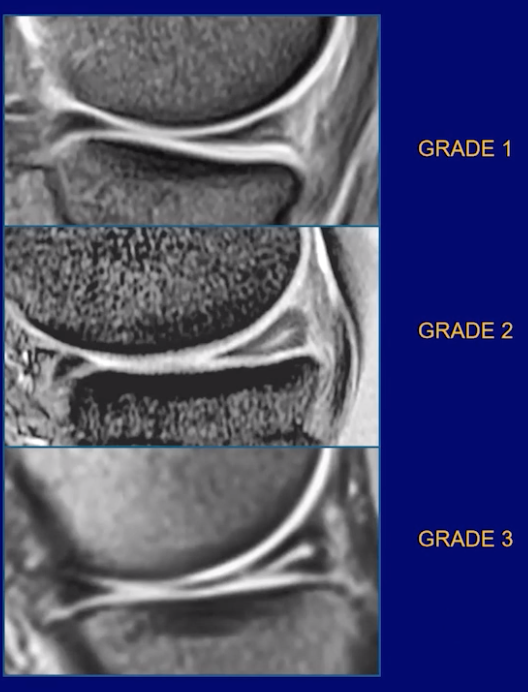

• Two slice touch rule

• Need abnormal signal contacting the meniscal surface on 2 slices in one or more planes

• Not all signal is pathology —> the intensity of the signal matters too —> see image

• Grade 1 —> likely normal

• Grade 2 —> likely degenerative shit

• Grade 3 —> likely tear

• If you see increased signal, these findings would make you think it is more benign

• Fades by the middle and near complete absent in the inner third

• Horizontally oriented

• Ok if it extends to the capsular surface = lateral edge of triangle (not ok if it extends to the articular surface = top and bottom)

• Not as bright as hyaline cartilage

• Is there adjacent swelling, bone contusion